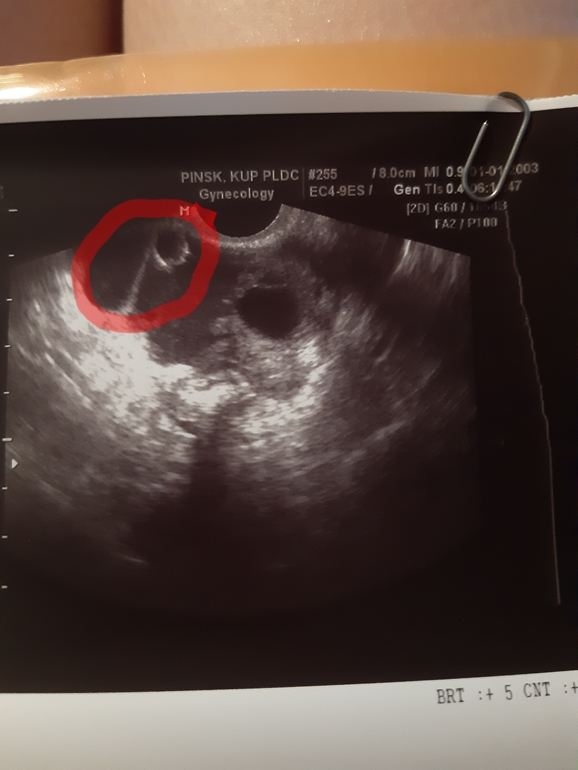

Была второй раз на УЗИ (13 д.ц.). Врач сказала что яичники визуализуруются слева, за маткой. Эндометрий подрос до 11 (что очень радует). Но вот что смущает: есть в позиматочном пространстве незначительное количество жидкости, и доминантный фолликул 16 мм... непонятно, но есть еще какое то образование, на кисту непохоже (т.к. не имеет контура, на фото в красном кокжочке). Сказала, что может это так видит овуляцию, но ведь есть доминантный фолликул. И в заключении написала ( во 2 фото).